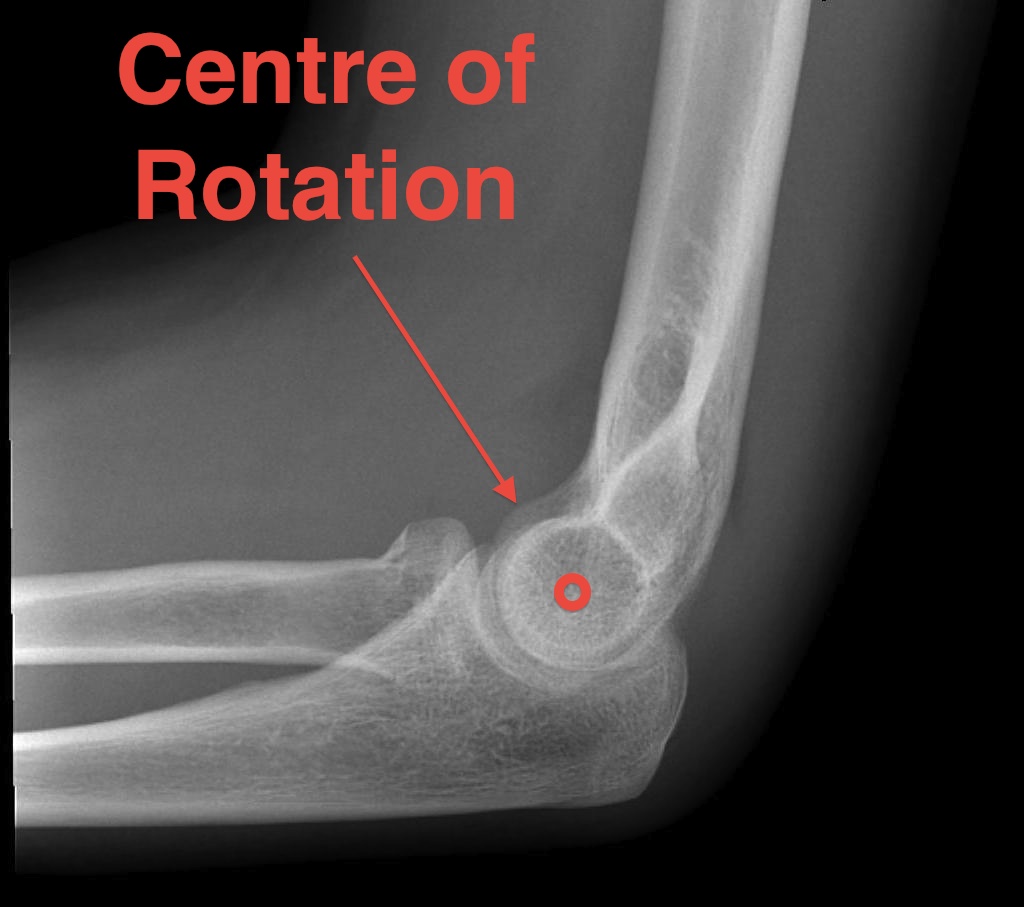

Centre of rotation - trochlea - centre of rotation anterior to humeral shaft |

- centre of rotation is center of capitellum